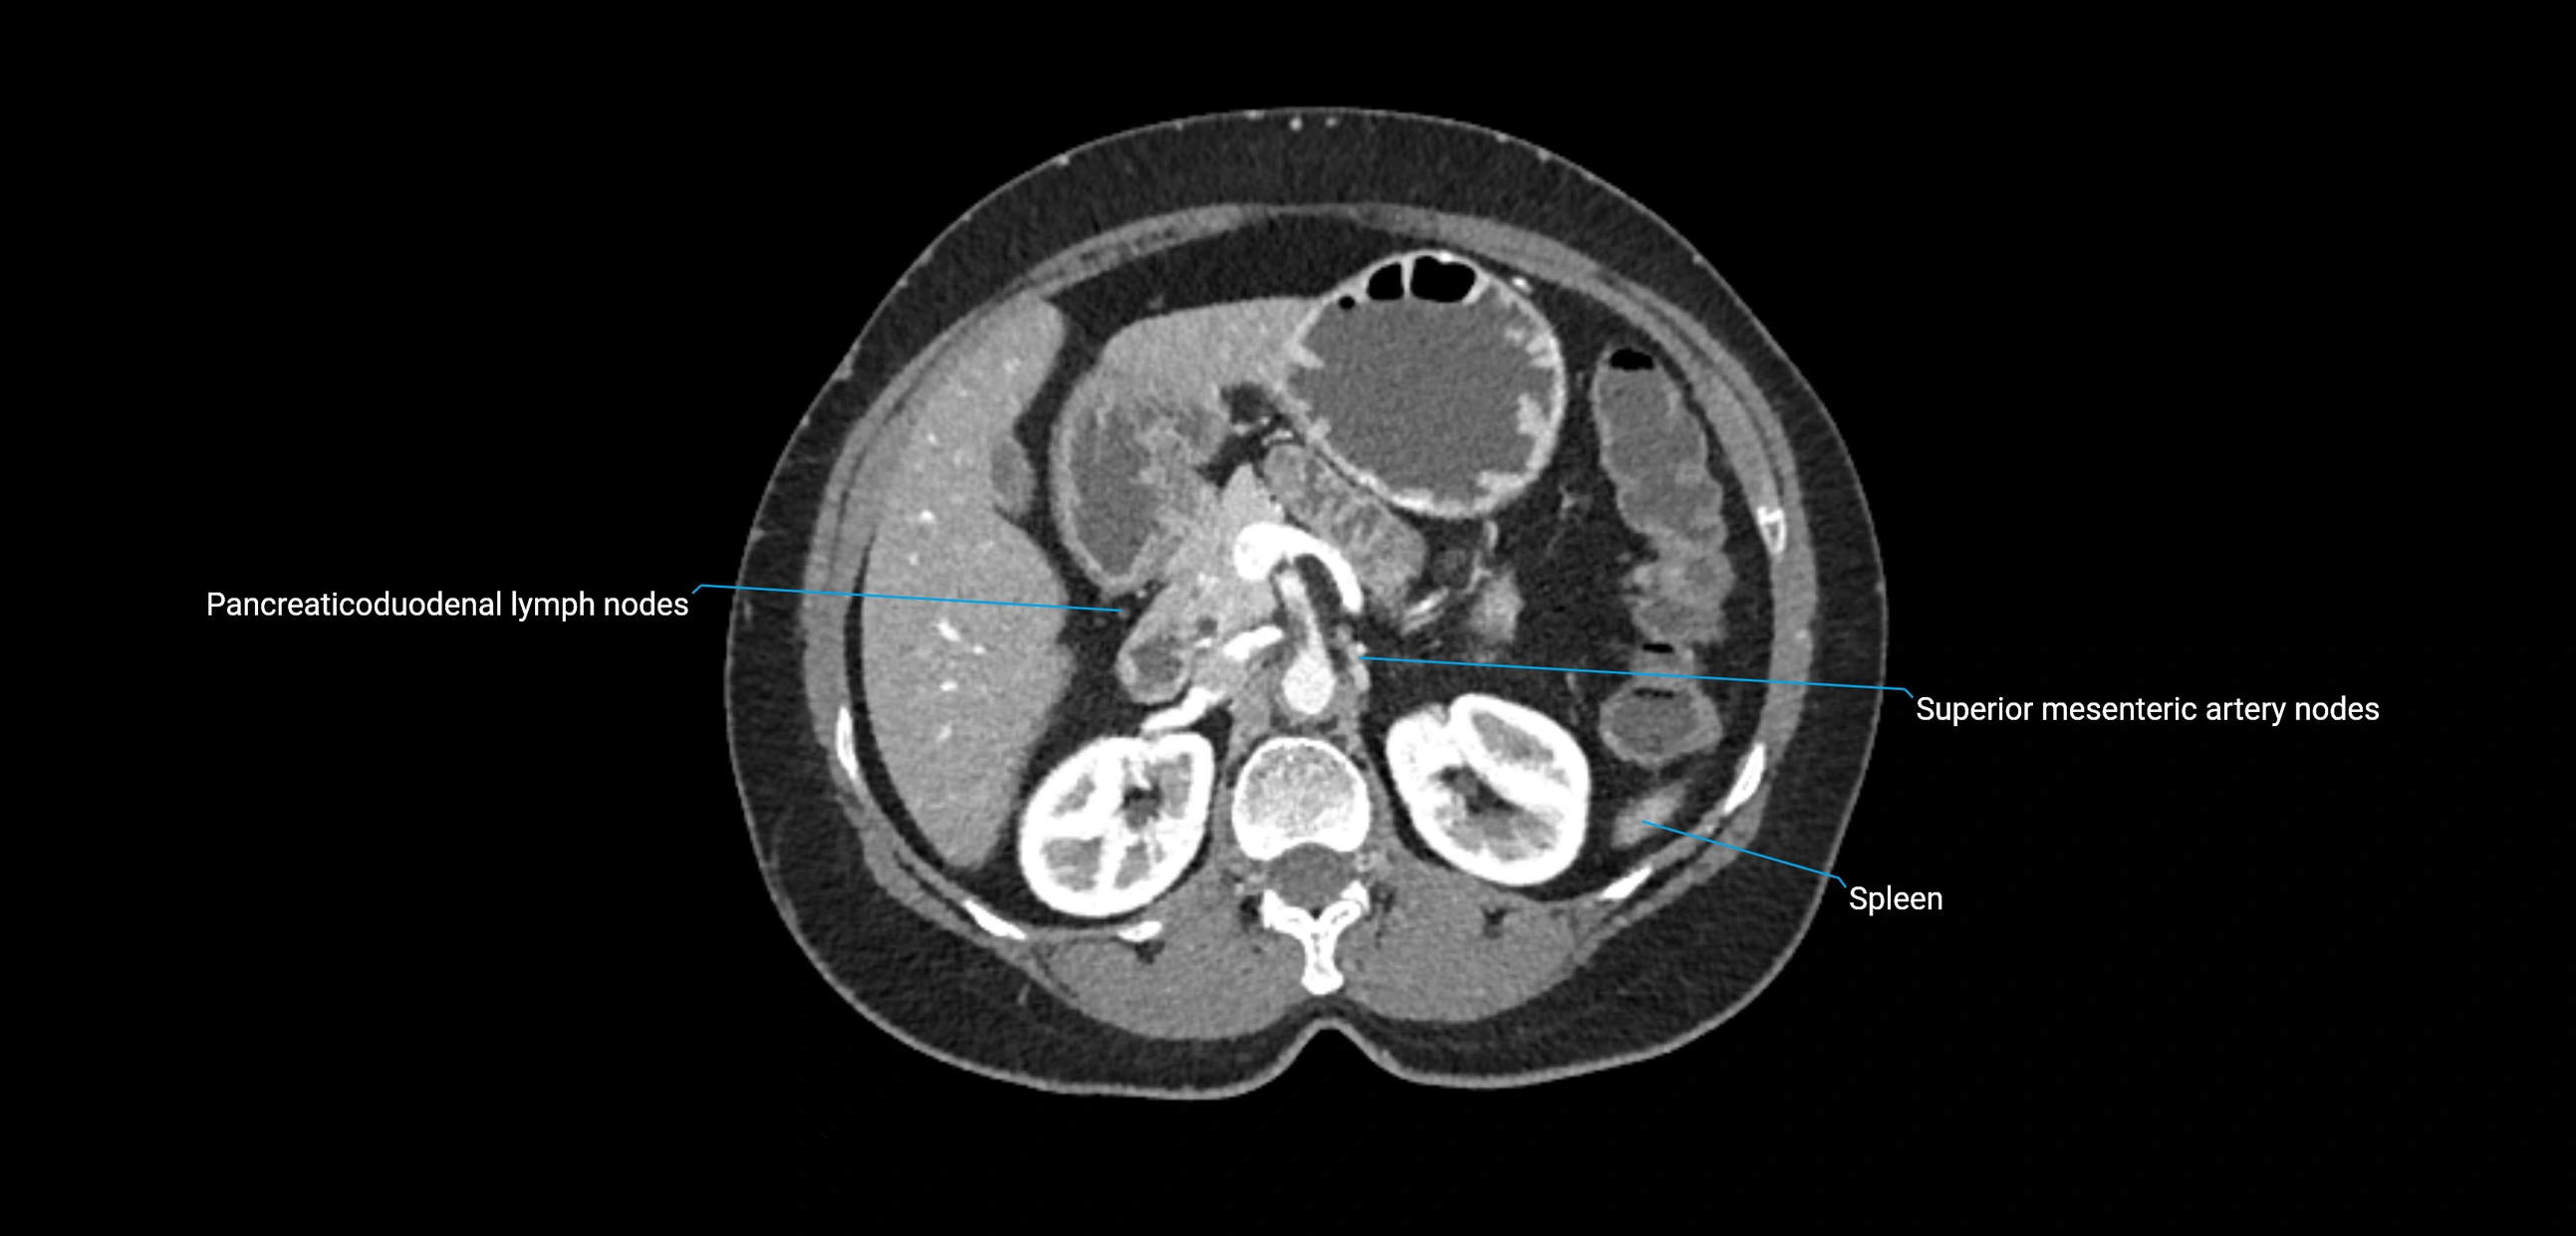

CT Appearance

CT Pre-Contrast:

• Nodes appear as soft-tissue density nodules adjacent to the aorta and IVC

CT Post-Contrast:

• Normal nodes enhance homogeneously

• Malignant nodes may show heterogeneous enhancement, central necrosis, or conglomerate formation

• Size >1 cm short axis is suspicious, though morphology and distribution are equally important